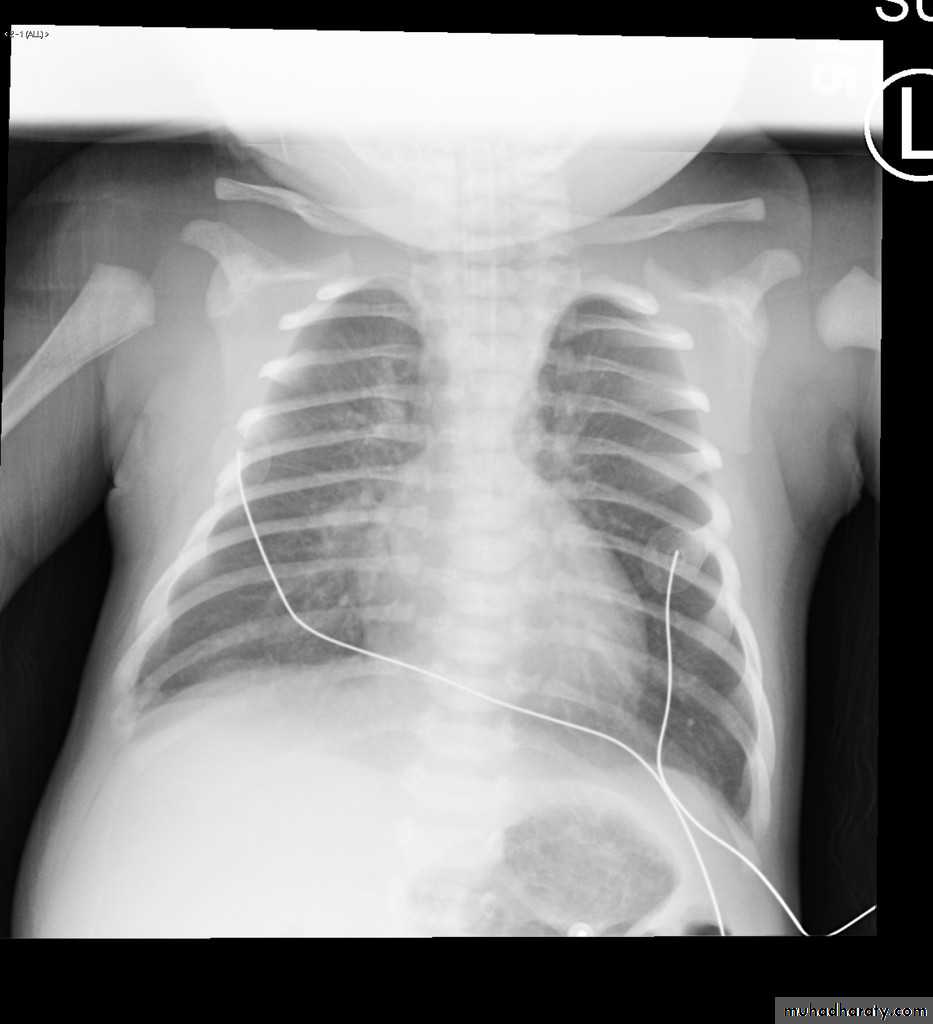

boot shape (wooden boot) heart (TOF)

CXR of a child, PA view shows:"boot shaped" heart with an upturned cardiac apex due to right ventricular hypertrophy and concave pulmonary arterial segment .

Pulmonary oligaemia due to decreased pulmonary arterial flow.